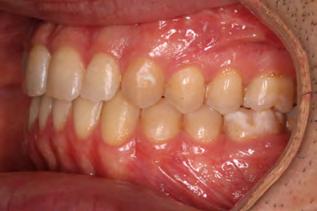

Approximately six months after insertion of the RPE, digital scans were taken for SureSmile custom wires and the patient was scheduled for the SFOT procedure with the oral surgeon. The RPE was removed, SureSmile wires inserted and segmental corticotomies performed, immediately followed by further vertical elastics on the right side (Figure

4). Archwires were upgraded incrementally into 19 x 25 SS. Once the bite was completely closed, the patient was referred to the myofunctional therapist to begin treatment. Eight sessions of myofunctional exercises were performed, focusing on muscle building, toning, synchronicity and awareness. Improvement in correct chewing, swallowing and resting postures of the lip and tongue were addressed. All appliances were removed 21 months after initial insertion (Figure 5), and the patient was referred to a re-

Figure 4. Post-corticotomy, with SureSmile custom wires.

storative dentist for veneers on the maxillary central incisors; the patient opted for gold veneers (Figure 6). Clear removable retainers were inserted with a fixed mandibular retainer canine-to-canine.

The patient finished with Class I occlusion, ideal overbite and overjet. The arches are co-

Figure 5. Final records.

ordinated, lateral open bite closed and occlusal cants leveled. From the frontal cephalometric tracings, maxillary width increased from 58 mm to 69 mm. From the lateral cephalometric tracing, the incisor angulations remained unchanged. The final report from the myofunctional therapist indicated the patient eliminated the bilateral posterior tongue-thrust swallowing pattern with saliva, liquid and solid swallows. Correct swallowing mechanics were demonstrated while sipping/gulping liquids from a cup. His day and nighttime tongue-resting postures were reported to be on his incisive papilla, with lateral margins lightly suctioned into the upper arch. Lips were closed and competent diurnally and nocturnally.

Most recent records are two years after removal of the orthodontic appliances, demonstrating the stability of the results (Figure 7).